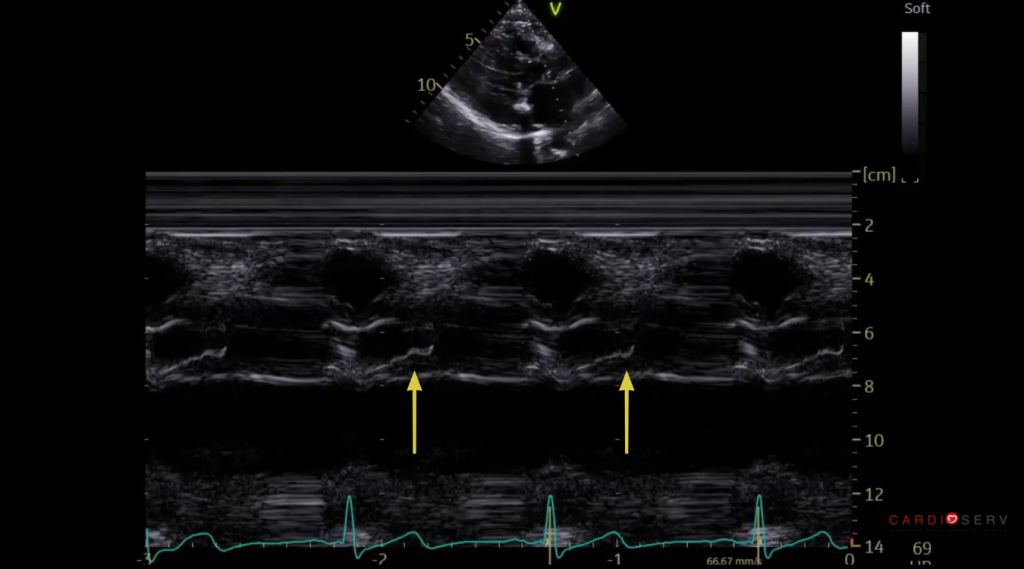

SAM on Aortic Valve M-mode

- Place your M-mode cursor through the aortic root and aortic valve leaflet tips in the parasternal long-axis (PLAX) view.

- On M-mode, the aortic valve opens normally, then partially closes halfway through systole before reopening, caused by a sudden decrease in flow due to obstruction.

These simple steps can make a subtle finding much more obvious and reproducible.